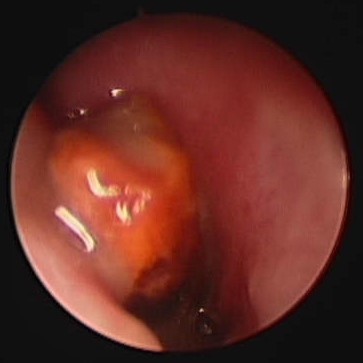

What is the probem here?

Destruction and white plaques – usually Aspergillus

What is the problem here?

See the destruction of the nasal cavity

Blind biopsy may help when you can see there is destruction

What is this? Where is it commonly found/how would we find it?

Nasal FB

Must check the internal nares too!

Retroflex and behind the soft palate